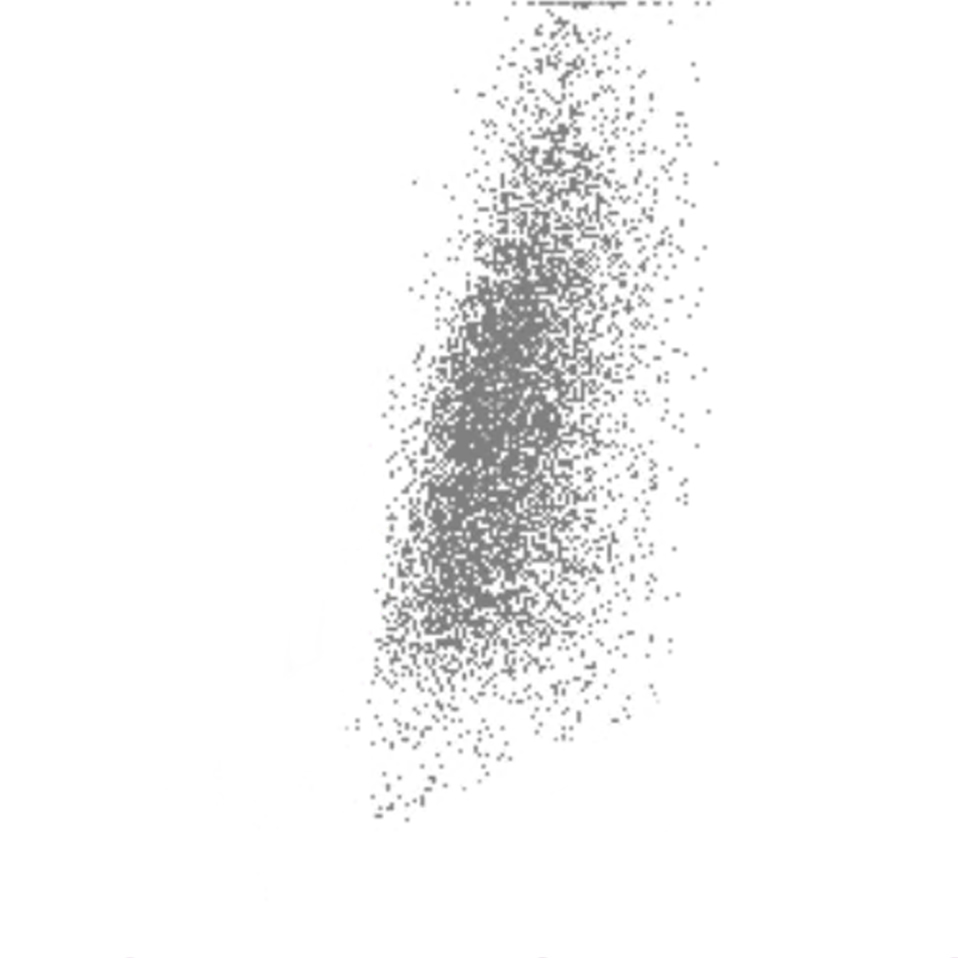

Side Scatter

La complexité cellulaire est principalement déterminée par la présence de structures intracellulaires telles que les granulations. Dans une moindre mesure, la forme du noyau (lobulation) et la présence de vacuoles jouent également un rôle. Dans le canal WDF du Sysmex, les éosinophiles présentent un SSC plus élevé que la normale en raison de l’effet du réactif sur leur granulation.

SSC scatter

SSC faible

SSC élevé